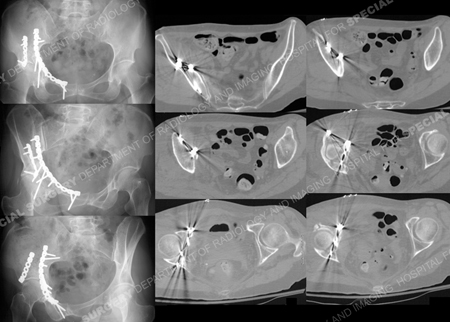

Postoperative anteroposterior and Judet radiographs (left) and postoperative CT scan images illustrating a satisfactory reduction and placement of hardware.